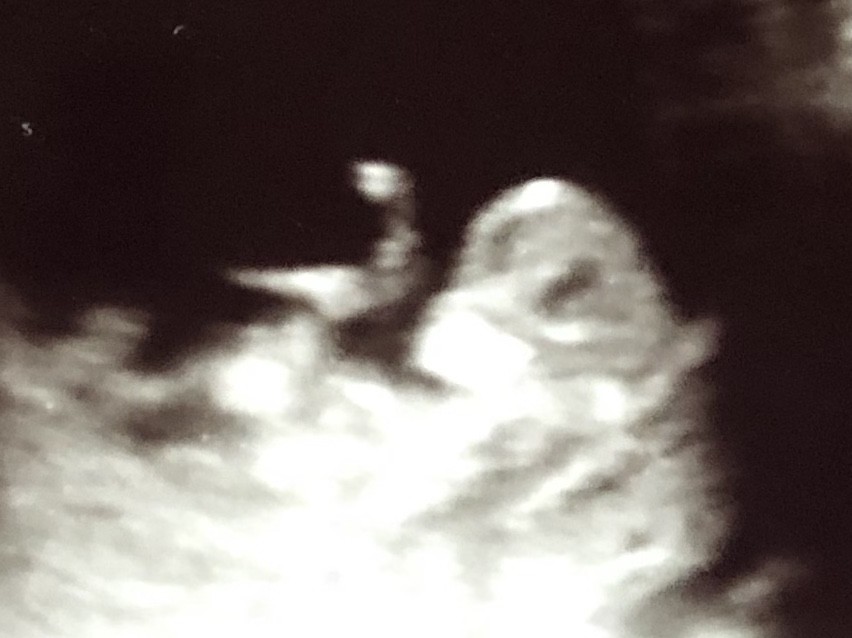

SadmiN ♥ Evli Mutlu Çocuklu ♥ Yönetici 20 Aralık 2019 #683 Malesef ilgili bölüm çok net değil yanlış bi tahminde de bulunmak istemiyorum cepten yakın çekip gönderebilir misiniz bi kaç tane çekin atın lütfen.

SadmiN ♥ Evli Mutlu Çocuklu ♥ Yönetici 20 Aralık 2019 #685 Yani çok net olmamakla birlikte erkek diyebileceğimi düşünüyorum.